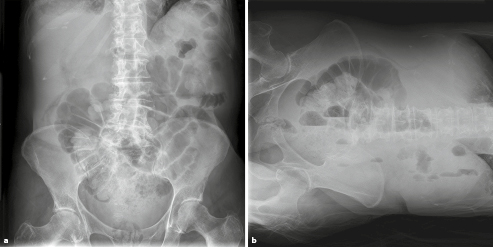

Mechanischer paralytischer Ileus 3. Therapie des mechanischen Ileus Abb3 Paent mit mechanischem Ileus Zur Verminderung der GI-Sekreon Butylscopolamin 40-120 mgTag sc oder Octreod03-06 mgTag sc Magensonde zur Entlastung Adäquate Schmerztherapie durchführen zB. Eine Ileus-Einleitung ist mit erheblichen Risiken behaftet.

Therapie des mechanischen Ileus Abb3 Paent mit mechanischem Ileus Zur Verminderung der GI-Sekreon Butylscopolamin 40-120 mgTag sc oder Octreod03-06 mgTag sc Magensonde zur Entlastung Adäquate Schmerztherapie durchführen zB.